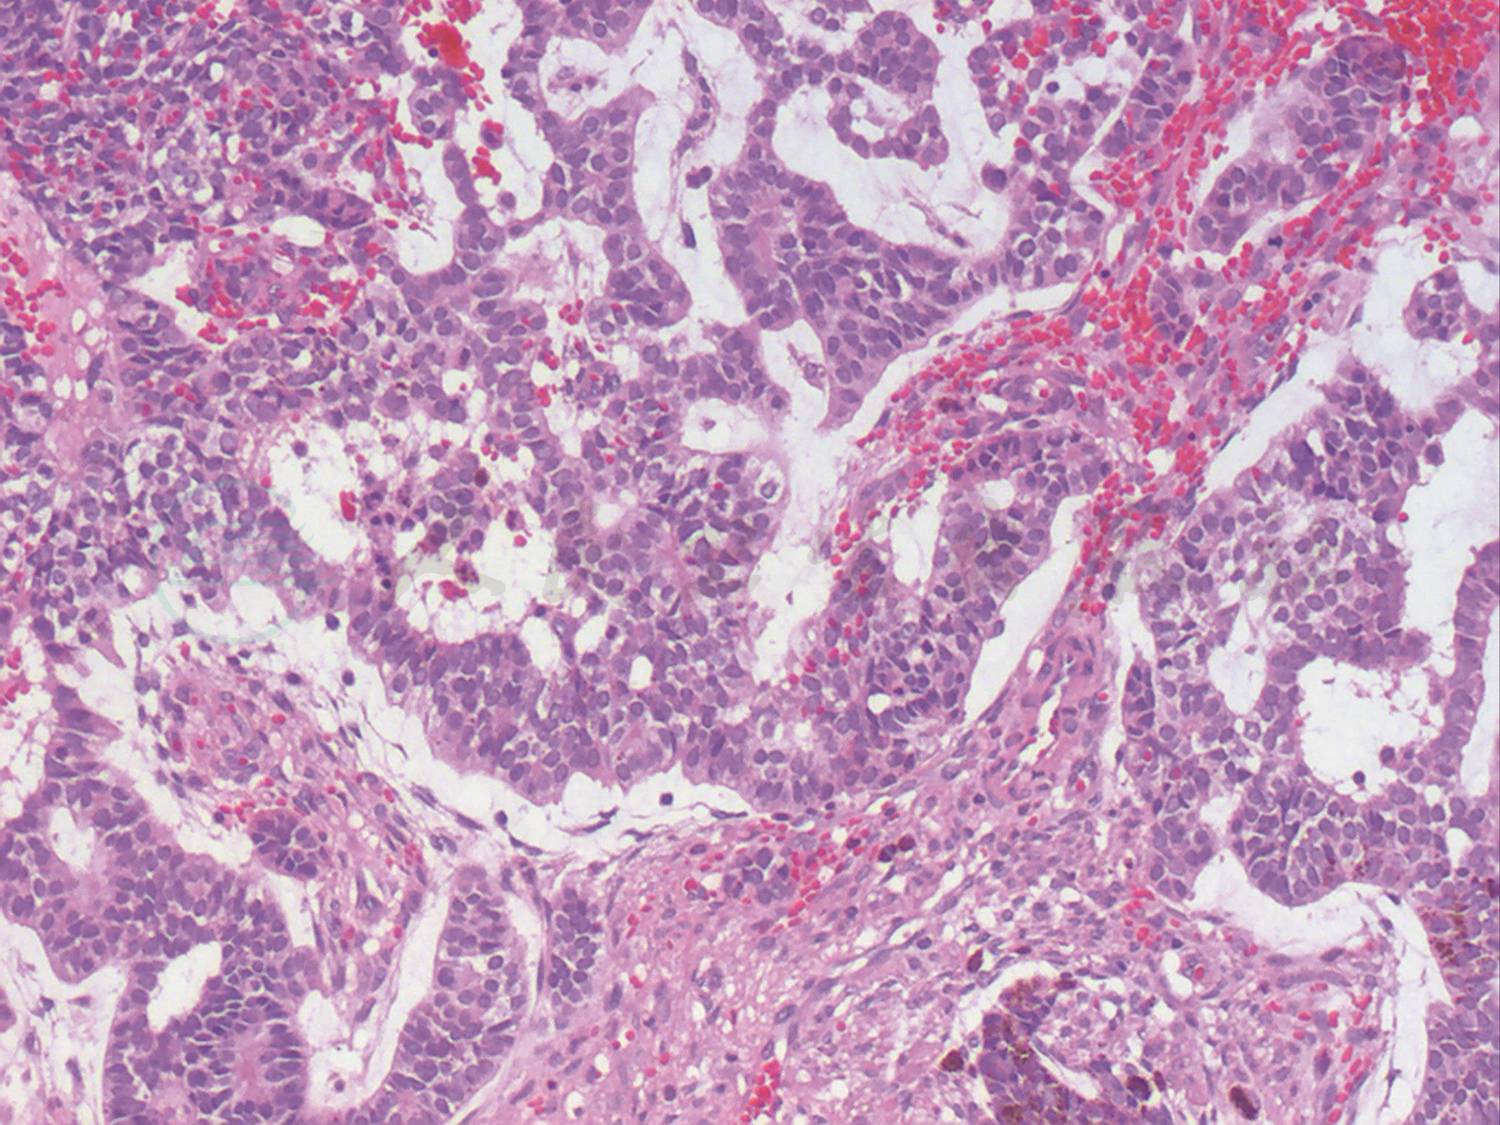

图2 眼眶MRI扫描影像结果

A.T1水平位,B.T2水平位,C.T1矢状位,D.增强水平位,显示左眼虹膜睫状体区可见实性占位性病变,增强扫描后可见肿瘤明显增强。

患儿男性,2.5岁,因发现左眼球内占位1个月就诊于首都医科大学附属北京同仁医院眼肿瘤科。患儿父母主述患儿1个月前玩耍时不慎碰伤左眼,就诊于当地医院,诊断为左眼前房积血,行眼部B型超声和眼眶CT检查后发现左眼球内占位性病变,提示视网膜母细胞瘤可能性大,故建议转诊首都医科大学附属北京同仁医院诊治。患儿既往身体健康,足月顺产,否认吸氧史及其他病史,否认家族遗传病史。患儿全身一般情况良好。眼部检查:双眼视力检查不合作,右眼眼压Tn,左眼T-1,左眼混合充血,角膜水肿、混浊,前房积血,眼内窥不清,左眼外斜视15△,眼球运动正常。右眼检查未见明显异常。本院眼部医学影像学检查结果:B型超声检查显示左眼眼轴较右侧缩短,左眼球内实性占位病变,不能排除视网膜母细胞瘤。CT扫描显示左侧眼球内高密度影并可疑性软组织影,外伤后出血机化可能性大,不能排除恶性病变可能(图1)。MRI扫描显示左侧眼球晶状体-虹膜-睫状体区占位性病变的可能性大,外伤后出血机化,形成增生性组织,恶性肿瘤待排除(图2)。血常规、尿常规及生化指标的实验室检查均未发现异常。

该病例的特点有:患儿2.5岁,年龄小;有外伤史;左眼混合充血,角膜水肿混浊、前房积血、左眼外斜视;B超示左眼球内实性占位,左眼轴较右眼短,提示左眼已经发生眼球萎缩,说明病史较长,病情较重;CT示左眼球内实性占位,可见钙化斑,如果没有外伤史,此种改变基本可以诊断为视网膜母细胞瘤;MRI示左眼病变累及部位为晶状体-虹膜-睫状体区域,而此区域却不是视网膜母细胞瘤发生的常见区域。